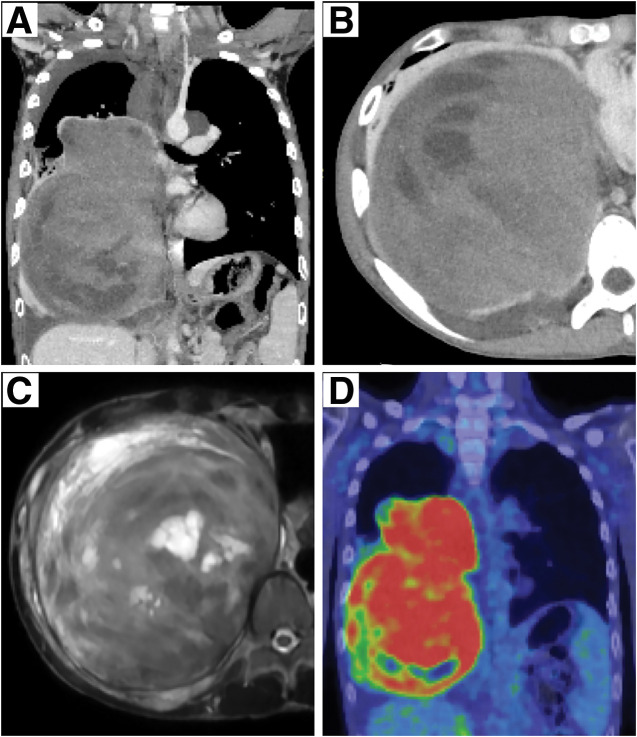

Case presentation: A 15-year-old boy presented with a large right mediastinal mass discovered on chest radiography at high school admission. Subsequent contrast-enhanced CT of the chest showed the development of a large tumor (16.0 × 12.5 × 11.8 cm) occupying approximately two-thirds of the right thoracic cavity, with atelectasis of the lower lobe of the right lung. The patient was histopathologically diagnosed with a benign schwannoma associated with neurofibromatosis type 1 through a thoracoscopic biopsy of the tumor and had received oral selumetinib at 50-70 mg/day for 11 months. Surgical excision was performed because of tumor progression and suspected malignant transformation. Right posterolateral thoracotomy with the opening of the 6th intercostal space was performed by extending the anterior skin incision along the abdominal rectus muscle and separating the 6th costal cartilage and diaphragmatic margin along the chest wall. The tumor was completely removed by resecting numerous adhesions between the tumor and the surrounding tissues and coagulating several nutrient vessels that flowed into the tumor, while resecting the lower lobe of the lung. The postoperative course was uneventful. The pathological examination revealed no malignancy. Subsequent contrast-enhanced CT of the chest revealed no residual tumors.